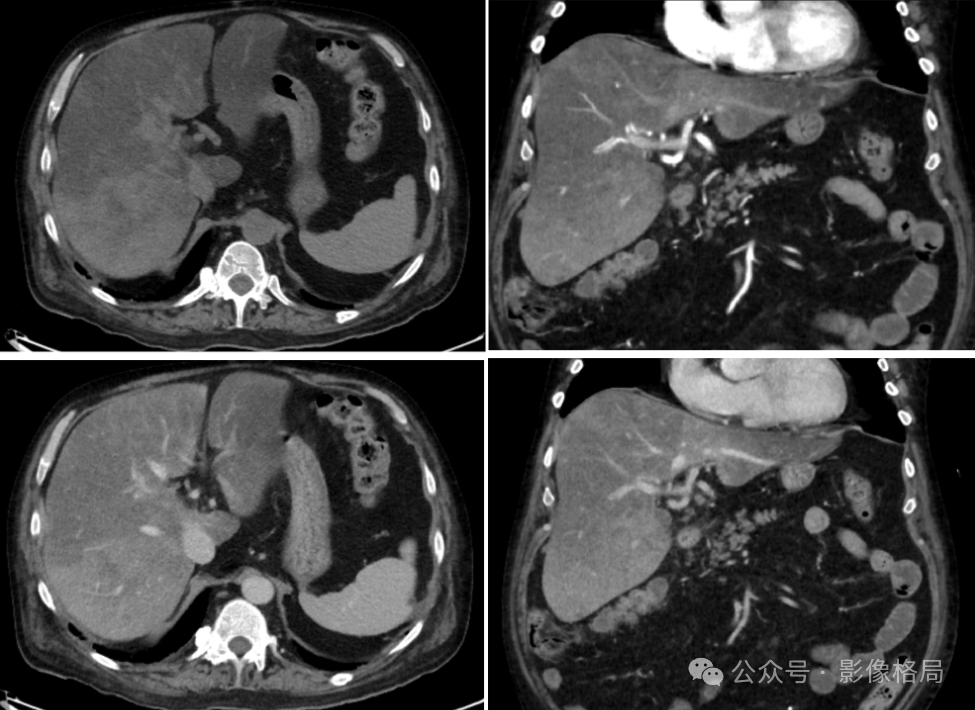

A 65-year-old female, multiple low-density lesions in the liver.

From left to right, top to bottom, are plain scan, arterial phase, venous phase, and delayed phase.

Heterogeneous signal in the liver, with a plain scan HU value of -4, indicating hepatic steatosis. No displacement or narrowing of vessels. No lymphadenopathy. No ascites.